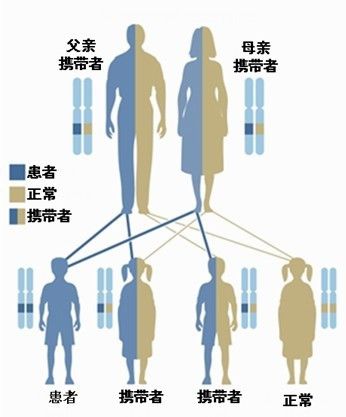

案例1:一对夫妻中有一方是带有显性致病基因,另一方则是带有一般(非致病)基因,他们的小孩会有50%的几率会带有相同的显性致病基因和50%几率带有一般(非致病)的基因。这代表在后代中会有 50%的几率会发病。

案例2:一对夫妻中有一方是带有一个隐性的致病基因,而另一方则是带有一般 (非致病) 基因,他们的小孩即有50%的几率会带有一个相同的隐性致病基因,和50%几率带有一般 (非致病) 的基因。这代表后代中会有50%几率把这个隐性基因在家族中持续遗传下去。

案例3:夫妻两人都带有一个隐性的致病基因,他们的小孩会有25%的几率带有两个隐性致病基因,50%的几率会带有一个的隐性致病基因,和25%几率带有一般 (非致病) 的基因。这代表在后代中会有25%的几率会发病,和50%几率把这个隐性基因在家族中持续遗传下去。